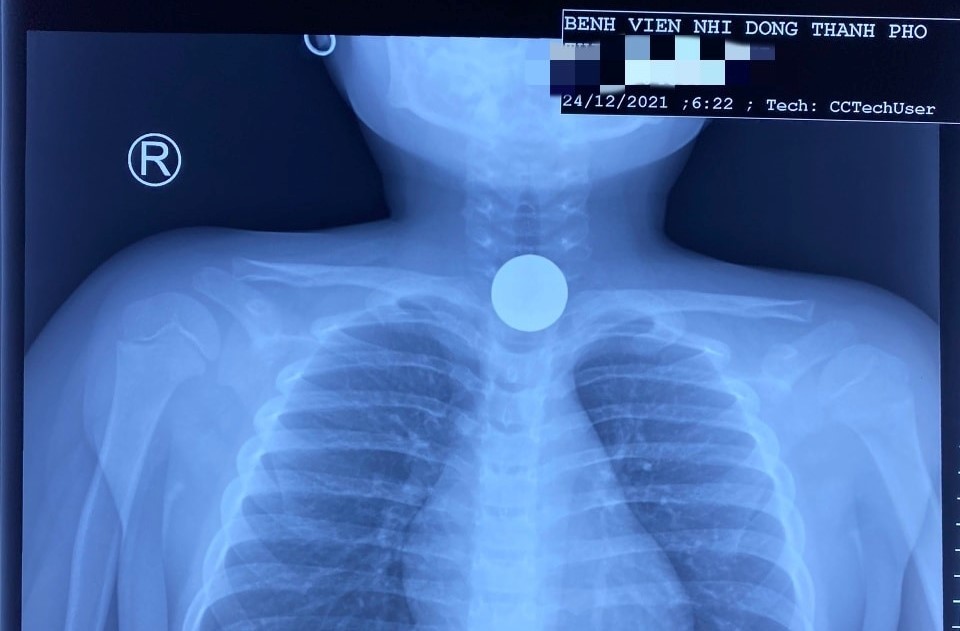

Bé 5 tuổi nuốt đồng xu, cấp cứu trong đêm giáng sinh

Khi người thân phát hiện cháu bé ói liên tục nên vội vàng đưa đến bệnh viện. Các bác sĩ đã gắp ra một đồng xu dùng để chơi game đang mắc ở thực quản.